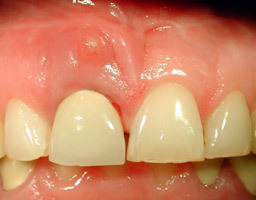

L’orthodontie a permis d’ouvrir un espace réduit et de poser un implant en site de la canine. La canine naturelle est absente depuis de nombreuses années.

Après la pose de l’implant, une empreinte est réalisée. La couronne provisoire est vissée 48 heures après.

La couronne provisoire doit être plus courte pour laisser l’ostéointégration de l’implant s’effectuer. La canine ne doit pas « travailler » et ne pas guider les mouvements de latéralité pendant 5 mois.